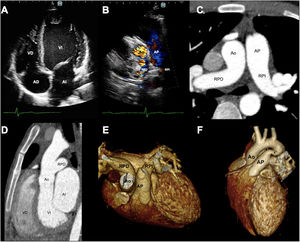

Varón de 18 años con disnea de esfuerzo moderado y hemoptisis desde hace 2 años. En el ecocardiograma se observó dilatación de cavidades izquierdas (fig. 1A, AD: aurícula derecha; AI: aurícula izquierda; VD: ventrículo derecho; VI: ventrículo izquierdo), origen anómalo de rama pulmonar derecha (RPD) desde la aorta ascendente (Ao) con origen normal de la rama pulmonar izquierda (RPI) (fig. 1B; arteria pulmonar [AP]) y función sistólica del VI del 55%. La angiotomografía computarizada confirmó los hallazgos por ecocardiograma (fig. 1C-E) y evidenció persistencia del conducto arterioso (fig. 1F, asterisco). Se obtuvo el permiso del paciente tanto para las pruebas como para la publicación del caso.

El cateterismo cardiaco derecho mostró hipertensión pulmonar (HTP) grave izquierda precapilar con presión arterial pulmonar media (PAPm) de 56mmHg, presión capilar pulmonar de 10mmHg, resistencia vascular pulmonar de 8,4 unidades Wood e HTP derecha con valores sistémicos (PAPm de 75mmHg y resistencia vascular pulmonar de 23,6 unidades Wood). El paciente decidió continuar solo con tratamiento médico.

El origen anómalo de una de las ramas de la AP a partir de la Ao es una malformación conotruncal infrecuente (0,1% de las cardiopatías congénitas) y grave. En esta afección, el pulmón conectado con la AP anómala está expuesto a presiones sistémicas de la Ao, mientras que el otro pulmón recibe todo el gasto cardiaco ventricular derecho, y tiene una sobrecarga de volumen, por lo que se recomienda la corrección quirúrgica a una edad temprana para evitar la enfermedad vascular pulmonar irreversible.